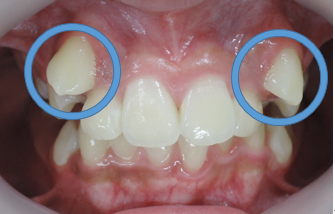

初診時

治療1年6カ月後

このように、1年6ヶ月間、通院して頂ければ治療計画どうりの目標は達成されます。

しかし、上下の顎骨の状態が改善されたからと言って永久歯が綺麗に並ぶわけではありません。

○印の中にある突起は永久歯の犬歯です。

但し、本来顎骨が劣成長であった場合はその中にある永久歯は著しい位置異常を起こしている場合が多い為に上下顎骨の大きさや咬み合わせの高さが改善したとしても、歯並びが悪くなる事がほとんどです。

その場合は永久歯の歯列矯正の計画の契約を結び永久歯の綺麗な歯並びと咬み合わせに改善していきます。